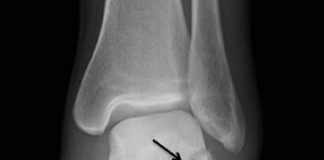

Aşil Tendon Rüptürü

Aşil tendonunun yırtılması, alt ekstremitede en sık görülen tendon yırtığıdır. Bu yaralanma genellikle üçüncü ile beşinci dekatlarındaki yetişkinlerde meydana gelir. Akut yırtılmalar, genellikle ani...